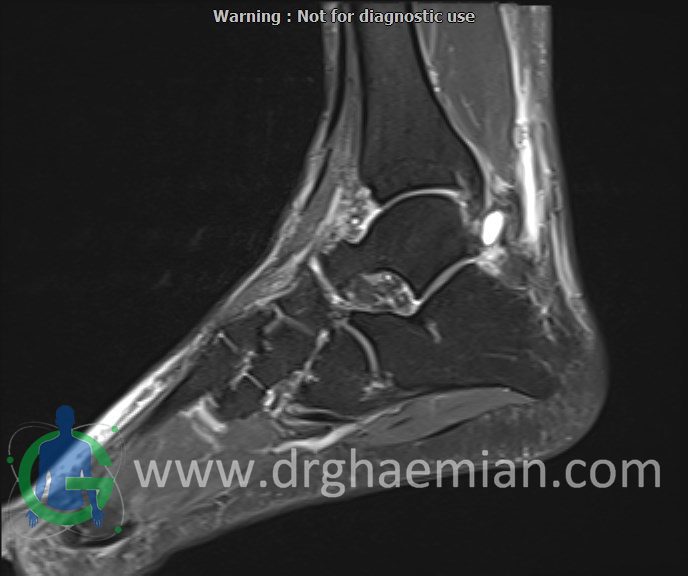

پزشکان اغلب از تصویربرداری ام آر آی برای تشخیص و درمان عارضه های پزشکی که فقط با استفاده از اشعه ایکس یا میدان مغناطیسی و امواج رادیویی قابل مشاهده است، استفاده می کنند. دستگاه ام آر آی تصاویر دقیق از ساختار های داخلی بدن ایجاد می کند. در این کیس کیست گانگلیون مچ پا بیمار مشاهده می شود.

Technique: Sagittal T1, T2 , Axial GE , coronal & sagital fatsat

soft tissue swelling around the ankle

signal change in posterior tibiofemoral ligament suggestive for sprain with traction bone bruise in tibia

ganglion cyst (7x13mm ) in posterolateral of ankle

soft tissue swelling around the lateral tubercle of talus with adjacent fat stranding suggestive for posterior impingement

are seen